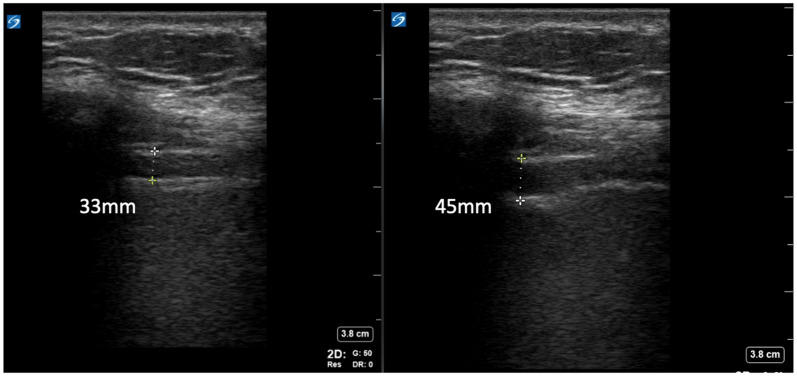

Methods: We used point-of-care ultrasound to evaluate ΔTDI% and diaphragm thickness during expiration (T exp) and inspiration (T insp) as predictors of extubation success in ESLD patients undergoing weaning from mechanical ventilation. The primary end-point was extubation tolerance (ET) assessed at 48 h.

Results: Of 70 enrolled patients, 82.4% (N = 56) tolerated extubation. While there was no difference in ΔTDI% between those who failed extubation (EF) compared to ET at 48 h (21.2% vs 20.1%, P = .64), diaphragms were thicker at expiration in ET patients (T exp 29.5 ± 8.1 vs 24.8 ± 5.2 mm, P = .047). Commonly used clinical weaning parameters, including rapid-shallow breathing index (RSBI) and negative inspiratory force (NIF) correlated better with diaphragm thickening fraction ΔTDI% than diaphragm thickness indices but were inferior predictors of extubation success compared to T exp..